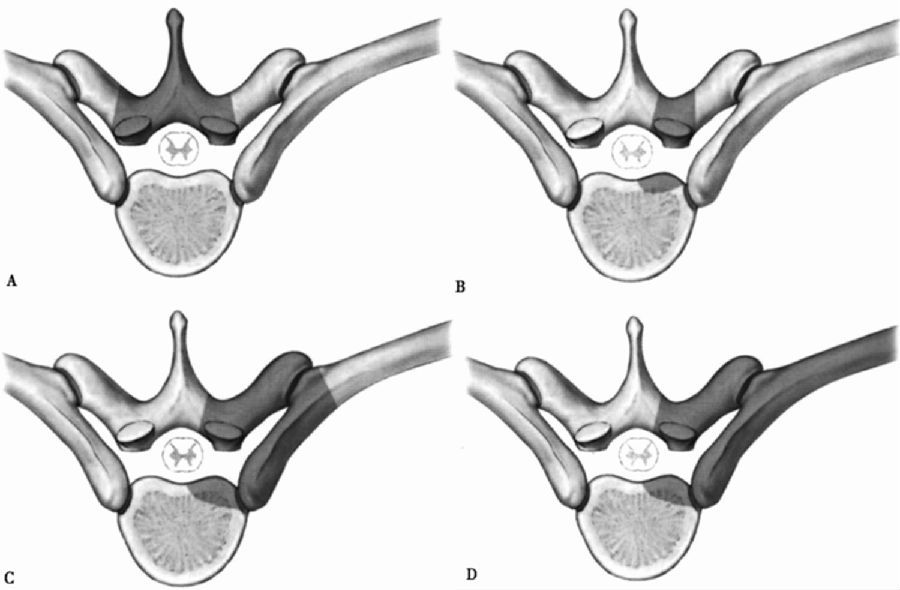

图1 胸椎后路手术入路

A:椎板切除术;B:经椎弓根和经关节突关节入路;C:肋横突切除术;D:外侧腔外入路